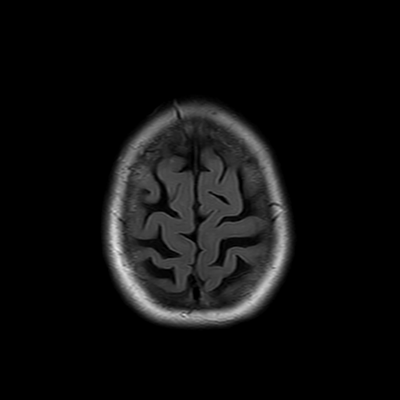

You also obtain an MRI of his brain once it's clinically safe to do so.

MRI brain (FLAIR)